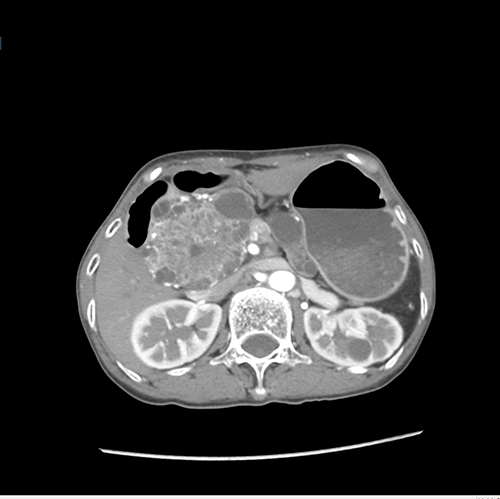

胰头囊腺瘤---胰十二指肠切除